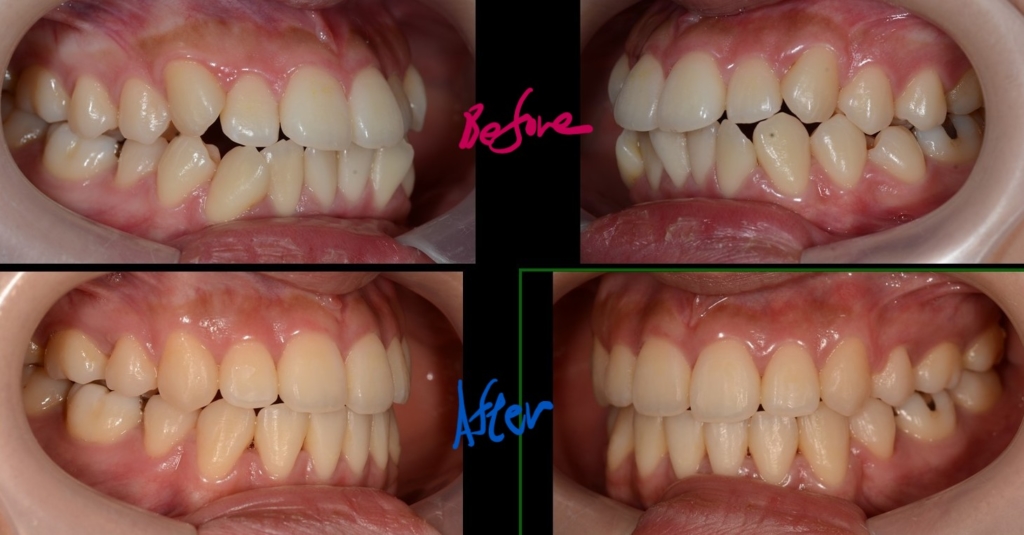

ついでに、歯並びの比較です

上段が矯正治療前、下段が矯正治療後